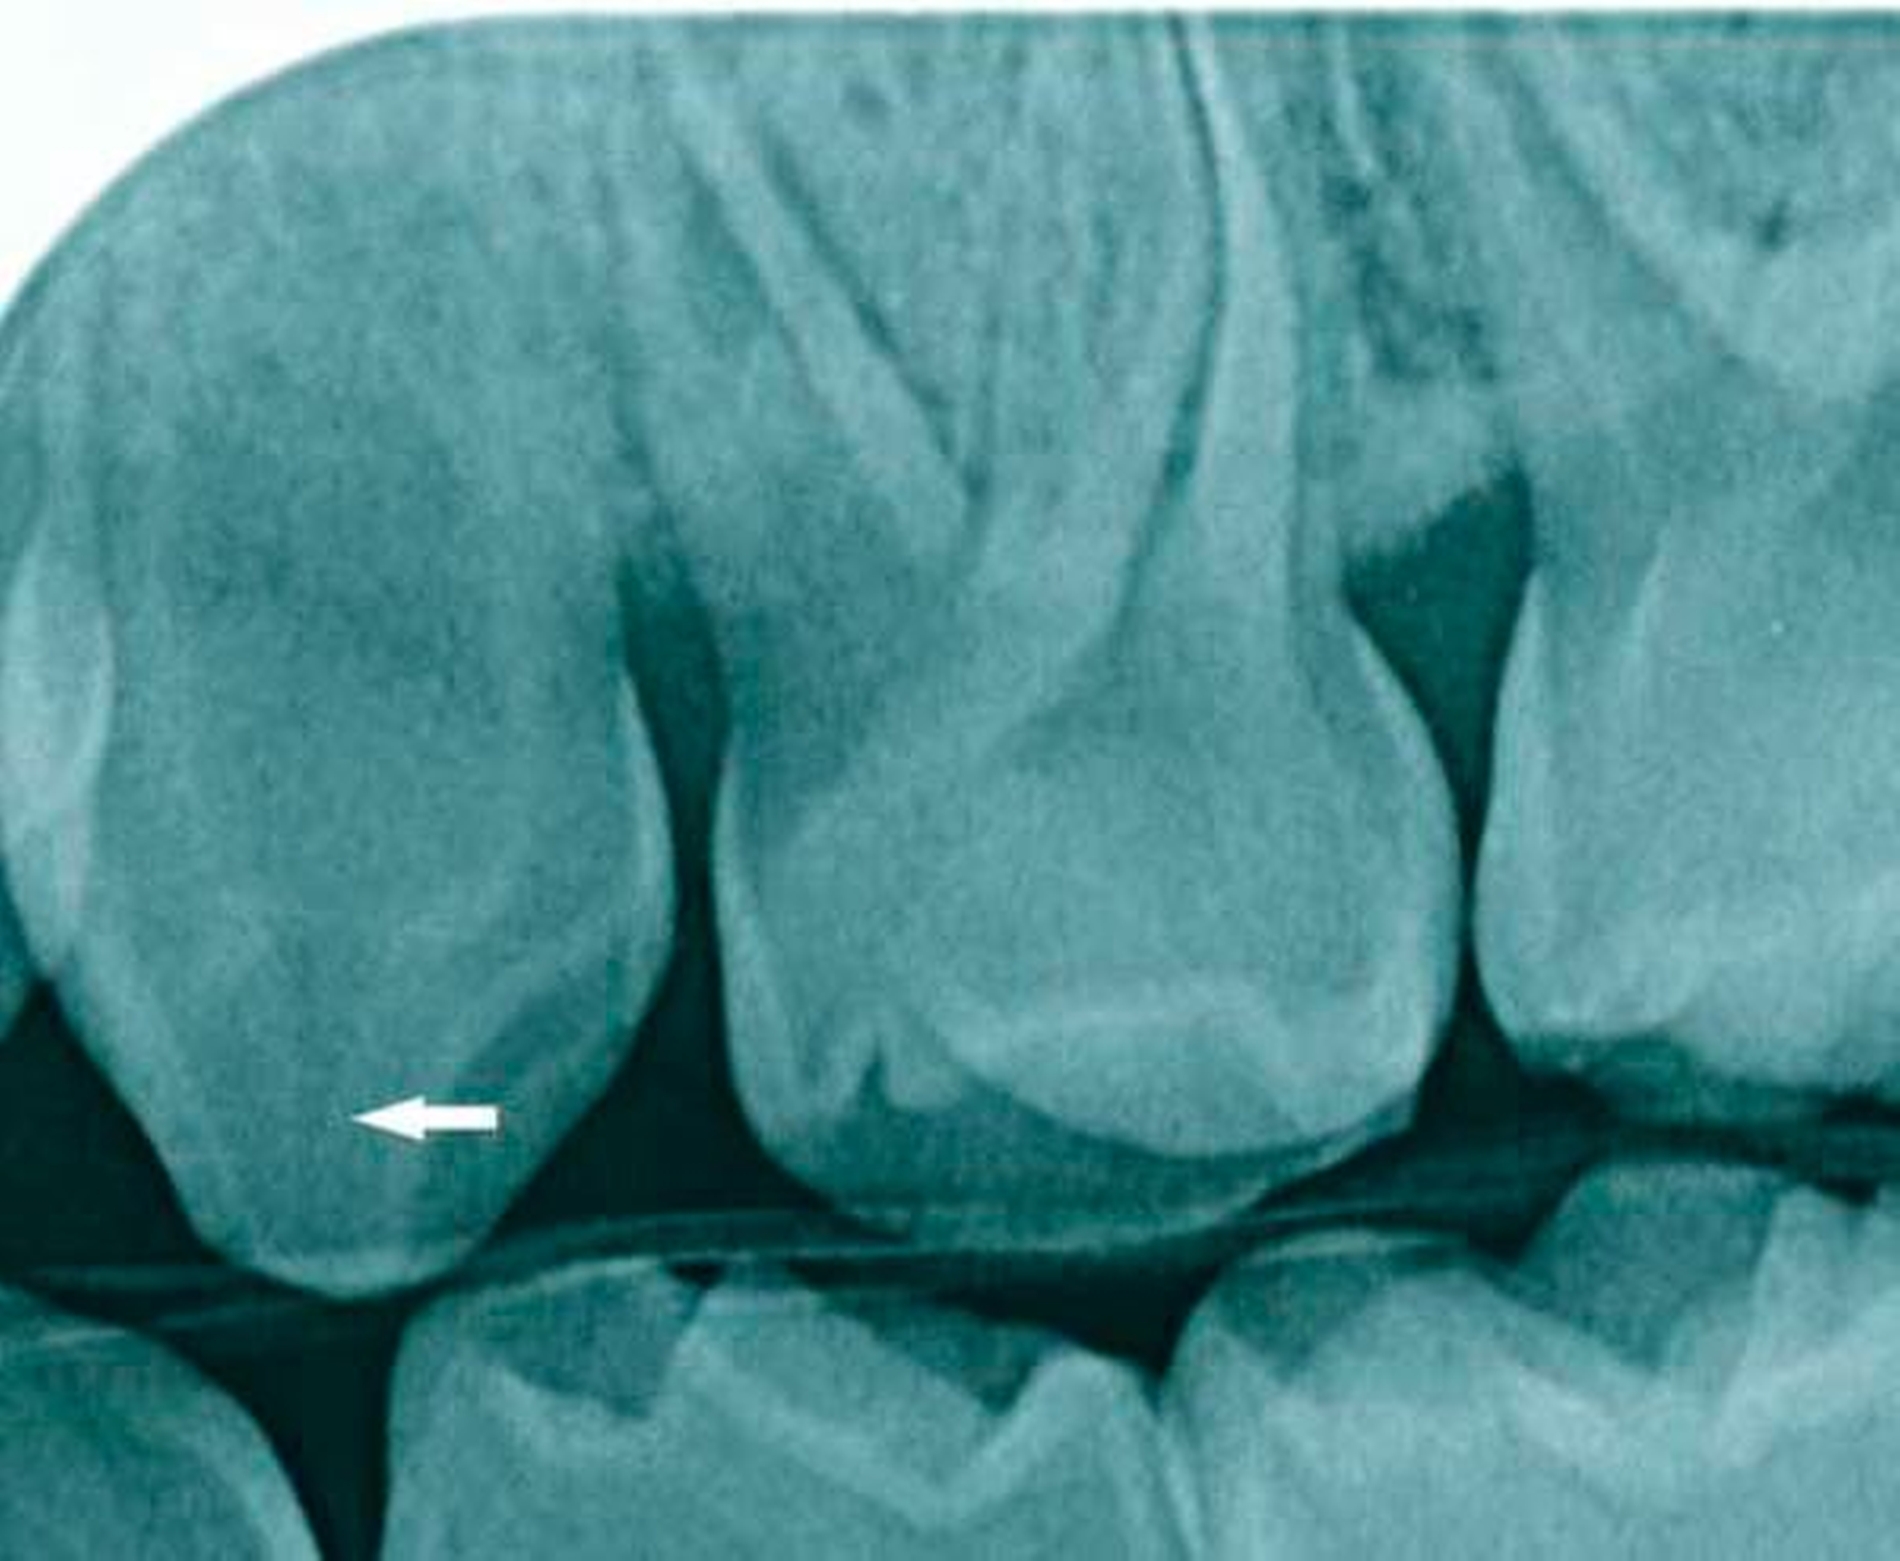

Ein dreijähriges Mädchen wird mit einem beginnenden Abszess der linken Fossa canina vorstellig. Klinisch zeigen die Zähne keinerlei kariöse Läsionen, die Ursache ist unklar. Radiologisch fällt ein ausgedehntes Pulpenhorn am Zahn 63 auf. Die Patientin ist insgesamt für ihr Alter eher kleinwüchsig. Allgemein anamnestisch liegt eine X-chromosomale Hypophosphatämie (Phosphatdiabetes) vor.

In histologischen Untersuchungen von Zähnen findet sich bei der X-chromosomalen Hypophosphatämie Interglobulardentin. Dies bedeutet, dass im Dentin eine unvollständig mineralisierte Dentinmatrix zwischen regulär mineralisierten Globuli vorliegt. Daneben fallen in histologischen Untersuchungen Ausdehnungen der Pulpa mit Pulpenhörnern und vergrößerten Pulpenkaven auf, die sich bis an die Schmelz-Dentin-Grenze ausdehnen, was eine Infektion der Pulpa begünstigt (Abbildung).

Infolge von Attrition des Zahnschmelzes können Bakterien durch das fehlgebildete und in seiner Struktur durchlässige Dentin in die bis an die Schmelz-Dentin-Grenze verzweigte Pulpa eindringen und zu Pulpanekrosen und Abszessen führen.